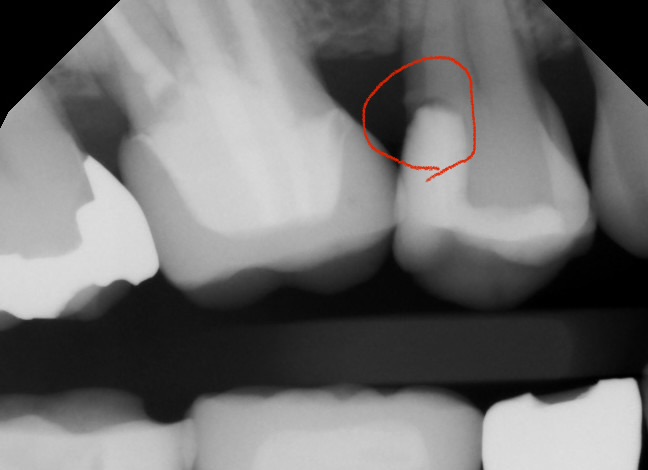

親知らずに押された7番が虫歯になってしまいました。